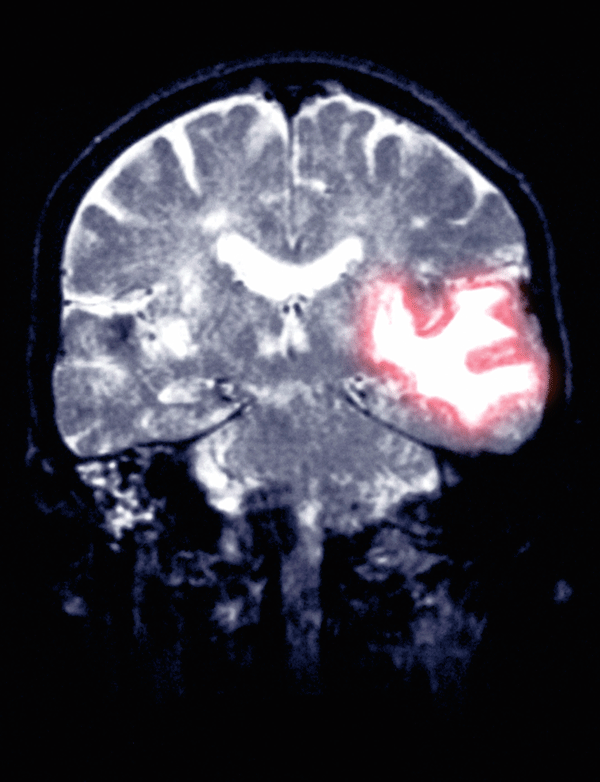

Das kraniale MRT einer 77-Jährigen zeigt eine Hirnblutung temporoparietal. Das kraniale MRT einer 77-Jährigen zeigt eine Hirnblutung temporoparietal. © Science Photo Library/Camazine, Scott